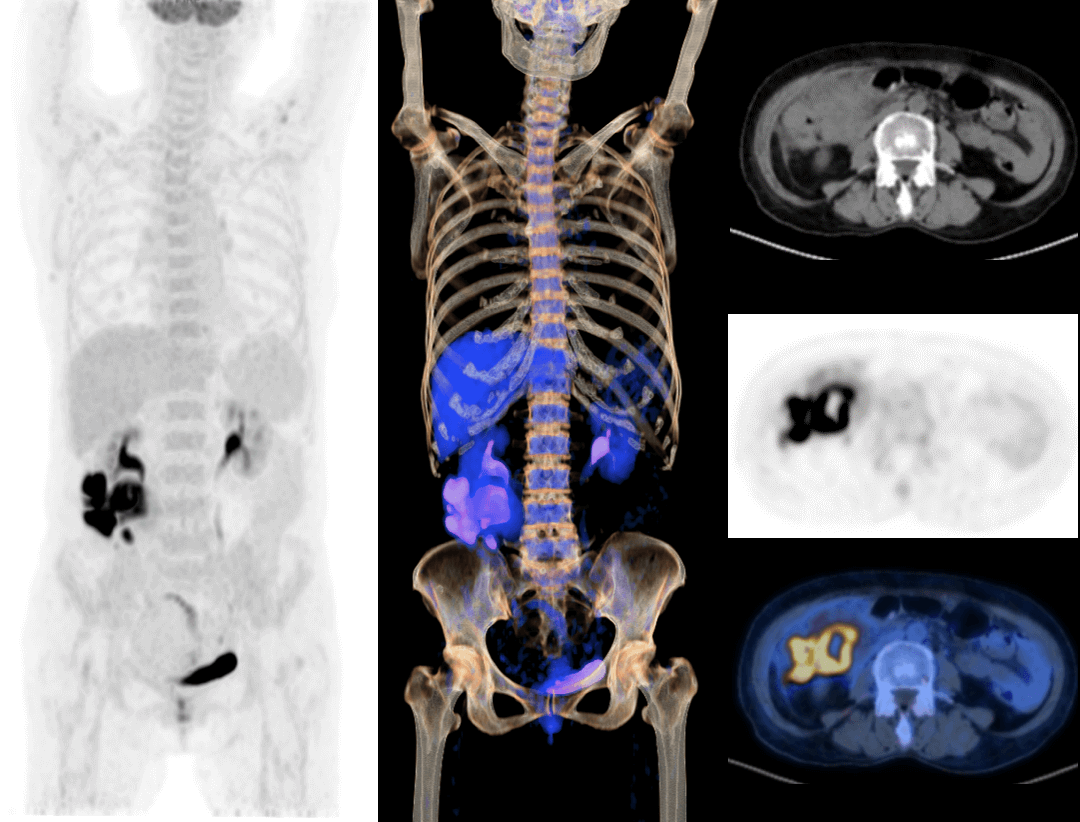

全真数字PET与160层北斗CT强强联手,将高品质的功能影像与解剖学影像精准融合,显著提升微小病灶检测精度,全面助力肿瘤、心脏和神经等重大疾病领域的精准诊疗。

2.9mm NEMA分辨率

硬件源头提升空间分辨率近40%*

*相较于空间分辨率为4mm的PET-CT系统

HYPER Iterative®4D全迭代算法

软件算法保障PET图像高清还原